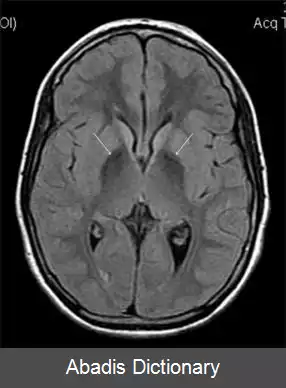

آسرولوپلاسمینمی. آسرولوپلاسمینمی ( به انگلیسی: Aceruloplasminemia ) نوعی ناهنجاری با توارث اتوزومی مغلوب است که طی آن آهن به تدریج در اندام های مختلف بدن تجمع میابد.

• دوران کودکی، نوجوانی و بزرگسالی: دیابت، آسیب شبکیه، علائم اکستراپیرامیدال، دیستونی، دیزآرتری و دمانس.